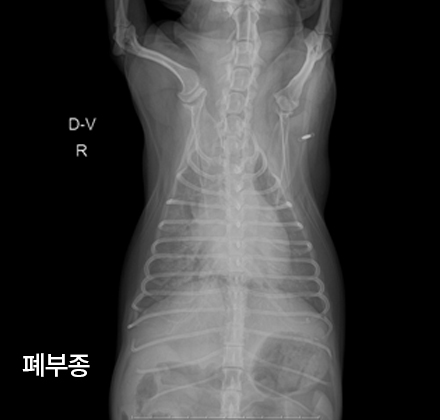

이런 응급 상황에선 어떤 치료를 받게 되나요?

산소치료

인공호흡치료

이뇨제 처치

혈관확장제 처치

안정

항부정맥 치료

제세동 치료LEE ANIMAL MEDICAL CENTER